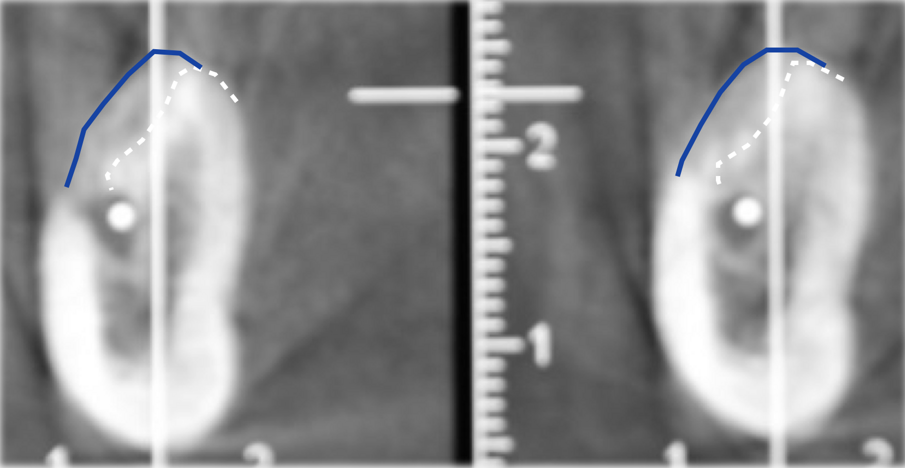

La sezione panoramica mise in evidenza la prossimità della cresta residua con il canale mandibolare (Figg. 3-4), e nei tagli sagittali si poté misurare come in prossimità delle due zone ove sarebbe stato interessante inserire gli impianti (primo premolare e primo molare) i volumi ossei residui non ne consentivano il posizionamento. Nel sito ove si voleva posizionare il primo premolare la distanza tra la cresta ossea e il tetto del canale mandibolare era di 5 mm, inoltre lo spessore della corticale sia vestibolare che linguale era ben rappresentato occupando 4 dei 5 mm disponibili per un eventuale sito implantare, inoltre il forame mentoniero si apriva proprio in corrispondenza di questo sito creando un ulteriore limitazione anatomica. Il sito più posteriore mostrava un ulteriore restringimento in senso sagittale e questo rendeva la clearance verticale 4 mm mentre anche in questo caso le corticali vestibolare e linguale occupavano la grande maggioranza dello spazio disponibile limitando il volume osseo disponibile a una quantità insufficiente a ricevere un impianto. La progettazione chirurgica e protesica del caso prevedeva un intervento con tentativo di ampliare la cresta ossea residua sia in senso orizzontale (almeno a 6/7 mm) che verticale (3/4 mm) per poter accomodare in completa sicurezza impianti della lunghezza di 8.5 mm. In questo caso si decise di optare per un materiale che offrisse la possibilità di ricostruire il volume nelle due dimensioni dello spazio e richiedesse una sola fase chirurgica, la lamina corticale7-11 (Figg. 7-11).

A sei mesi dall’intervento chirurgico la paziente venne sottoposta ad una nuova CBCT di controllo e questa evidenziò come i volumi stavano cambiando e l’osso innestato si stava mineralizzando al di sotto della lamina corticale, in bianco si nota la variazione volumetrica rispetto a quella che era la condizione iniziale (in blu) (Fig. 13). A dodici mesi dal primo intervento si decise di intervenire per inserire nella zona due impianti come da progetto iniziale, dopo aver anestetizzato la paziente con Articaina 1:200.000 una nuova incisione a mezza cresta permettè di scostare i lembi vestibolari e linguali per esporre la nuova cresta ossea ora con uno spessore di 8 mm nella parte posteriore e 6 mm nella porzione più anteriore. Questo consentì il posizionamento di due impianti a vite Bredent uno di diametro 4.5 x 8,5 mm di lunghezza (nel sito del molare) e uno di diametro 4 x 8,5 mm di lunghezza nel sito del secondo premolare13 (Figg. 14, 15).